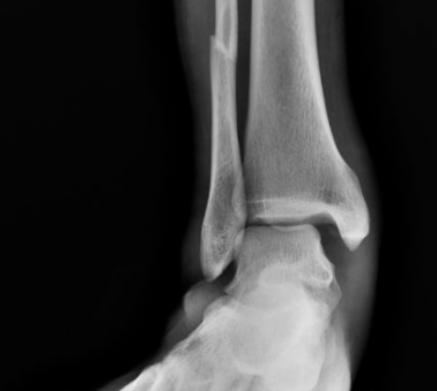

#踝关节骨折

踝关节撞击综合征!